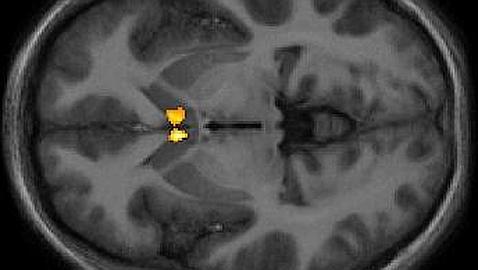

El amor activa zonas del cerebro relacionadas con las buenas experiencias (en la imagen, en color)

«Con la prueba de la distracción, las vías que condujeron al alivio del dolor fueron en su mayoría cognitivas», dice Younger, mientras que el alivio inducido por el amor estaba más asociado a los centros de recompensa. Parece que involucra aspectos más primitivos del cerebro, de forma similar a cómo funcionan los analgésicos opioides. «Uno de los sitios claves para la analgesia inducida por el amor es el núcleo accumbens, un centro de recompensa clave para la adicción a los opiáceos, cocaína y otras drogas. La región le dice al cerebro que realmente necesita seguir haciendo esto», dijo Younger.